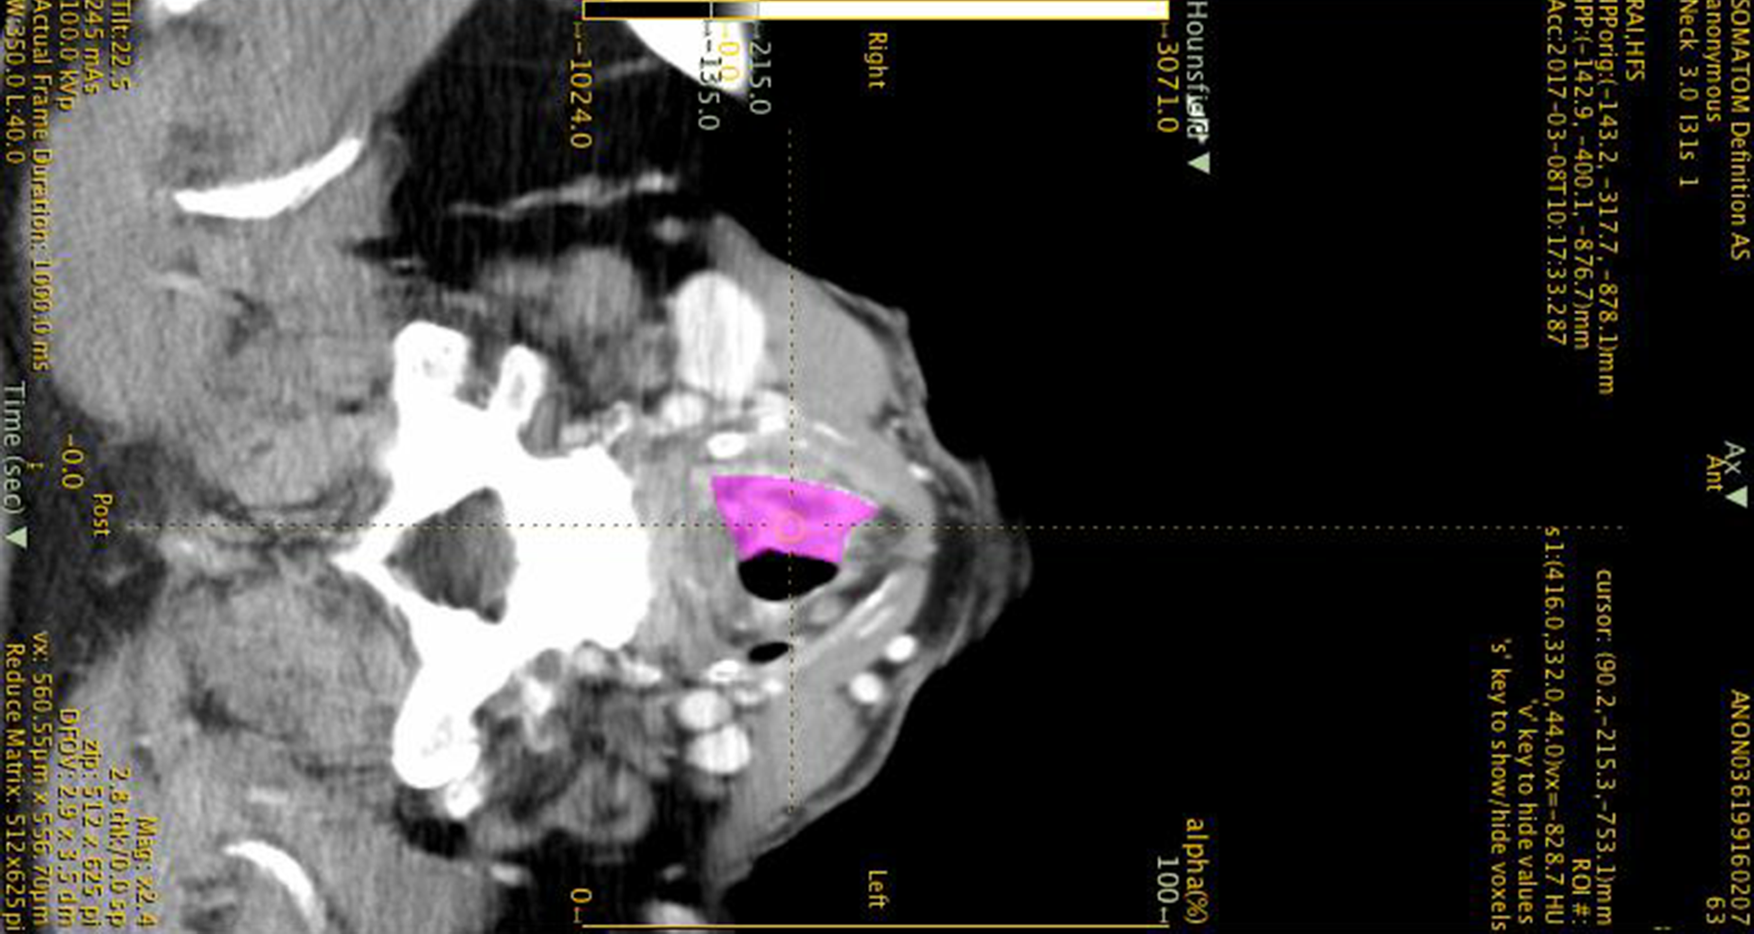

Image Processing

Laryngeal Cancers Biomarkers

Advanced laryngeal cancers are clinically complex; there is a paucity of modern decision-making models to guide tumour-specific management. This pilot study aims to identify computed tomography-based radiomic features that may predict survival and enhance prognostication.